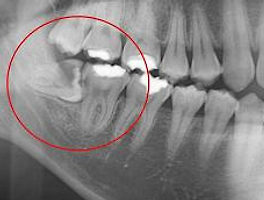

의자에 앉자마자 보이는 인형. 나중에 꼭 끓여서 앉아야지.오른쪽에 살짝 누워있어 신경이 마치 닿아보이는 듯한 나의 매복 사랑니..우선 마취를 하기 전에 가글제를 주시는데, 이것도 조금 마취 효과가 있다고 하네요.한 5분 정도 머물고 있었어요.옆 마스크 스탠드에 마스크를 벗고 얌전히 기다리고 있는 나..하지만 마음은 얌전하지 않아 TT(´;ω;))기다리시면서 다시 수술 전 주의사항과 안내사항에 대해서 말씀해주시는데 특이한 점은 지혈제를 매복 사랑니를 빼고 안에 넣게 되는데 이 지혈제가 녹아서 지혈이 되면서 개당 가격이 2.5 정도였던 것 같아요!엑스레이와 CT 촬영 결과 다행히 정신을 잃고 걱정 없다고 말씀해 주셨습니다.그래도 뿌리가 깊어서 뿌리가 남을 수도 있지만 최대한 예쁘게 뽑아주신다고 하셨죠!마취를 했더니 가슴 두근거림과 갑작스러운 졸음이 있어서 물어보니 괜찮다고 해서 안심했습니다.마취를 할 때 조금 쓰리고 아프지만 참을 수 없을 정도는 아니었어요.마취가 끝나고 10~15분 정도 기다리다가 바로 시작했어요.거짓말이 아니라 정말 5분도 안 돼서 끝난 것 같아서 고를 때는 전혀 아프지 않았어요.뿌리까지 너무 예쁘게 뽑혔다고 말씀해 주셨어요.끝나고 나서 주의 사항에 대해 물어보고 얼음 팩과 거즈를 준비해 주었습니다.발치 후 엑스레이 다시 찍어서 예쁘게 뽑혔는지 다시 확인하시고 사진도 문자로 보내주세요!지혈제 덕분인지 2시간이 지나서 집에 와서 거즈를 뽑았더니 피가 별로 젖지 않았고 통증이 있어서 바로 처방해준 약을 먹고 조금 기다렸는데 그때부터는 No 통증! 거즈도 필요 없었고 얼음찜질이라고 처방해준 약을 잘 먹었습니다.정말 깔끔하고 이렇게 사랑니 말고 안 아픈 건 처음이라 제 친동생도 바로 이틀 뒤로 예약했어요.ㅋㅋㅋ 동생아 화이팅.사랑니를 부탁드립니다.구강악안면외과 치과의원 : 네이버 방문자 후기 673 블로그 후기 83naver.me지혈제 때문인지 가격은 조금 나왔지만 아프지 않은 분들이 제일 최고, 정말 제 돈의 내산찜 후기 지인들에게 꼭 추천하고 싶은 사랑니 발치 병원입니다.정말 이웃분들도 사랑니 고민하시는 분들이 계시다면 여기 가보세요.나는 정말 아프지 않다는 것이 믿기지 않습니다.www그러면 곰득이네 집은 또 다른 포스팅으로 찾아뵙겠습니다.#매복사랑니 #사랑니발치 #사랑니발치전문병원 #사랑니부탁치과 #압구정치과 #사랑니발치병원 #사랑니발치전문병원추천 #사랑니발치추천 #사랑니발치병원추천 #압구정사랑니발치 #사랑니발치